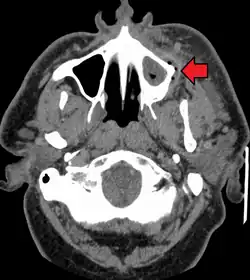

.jpg)